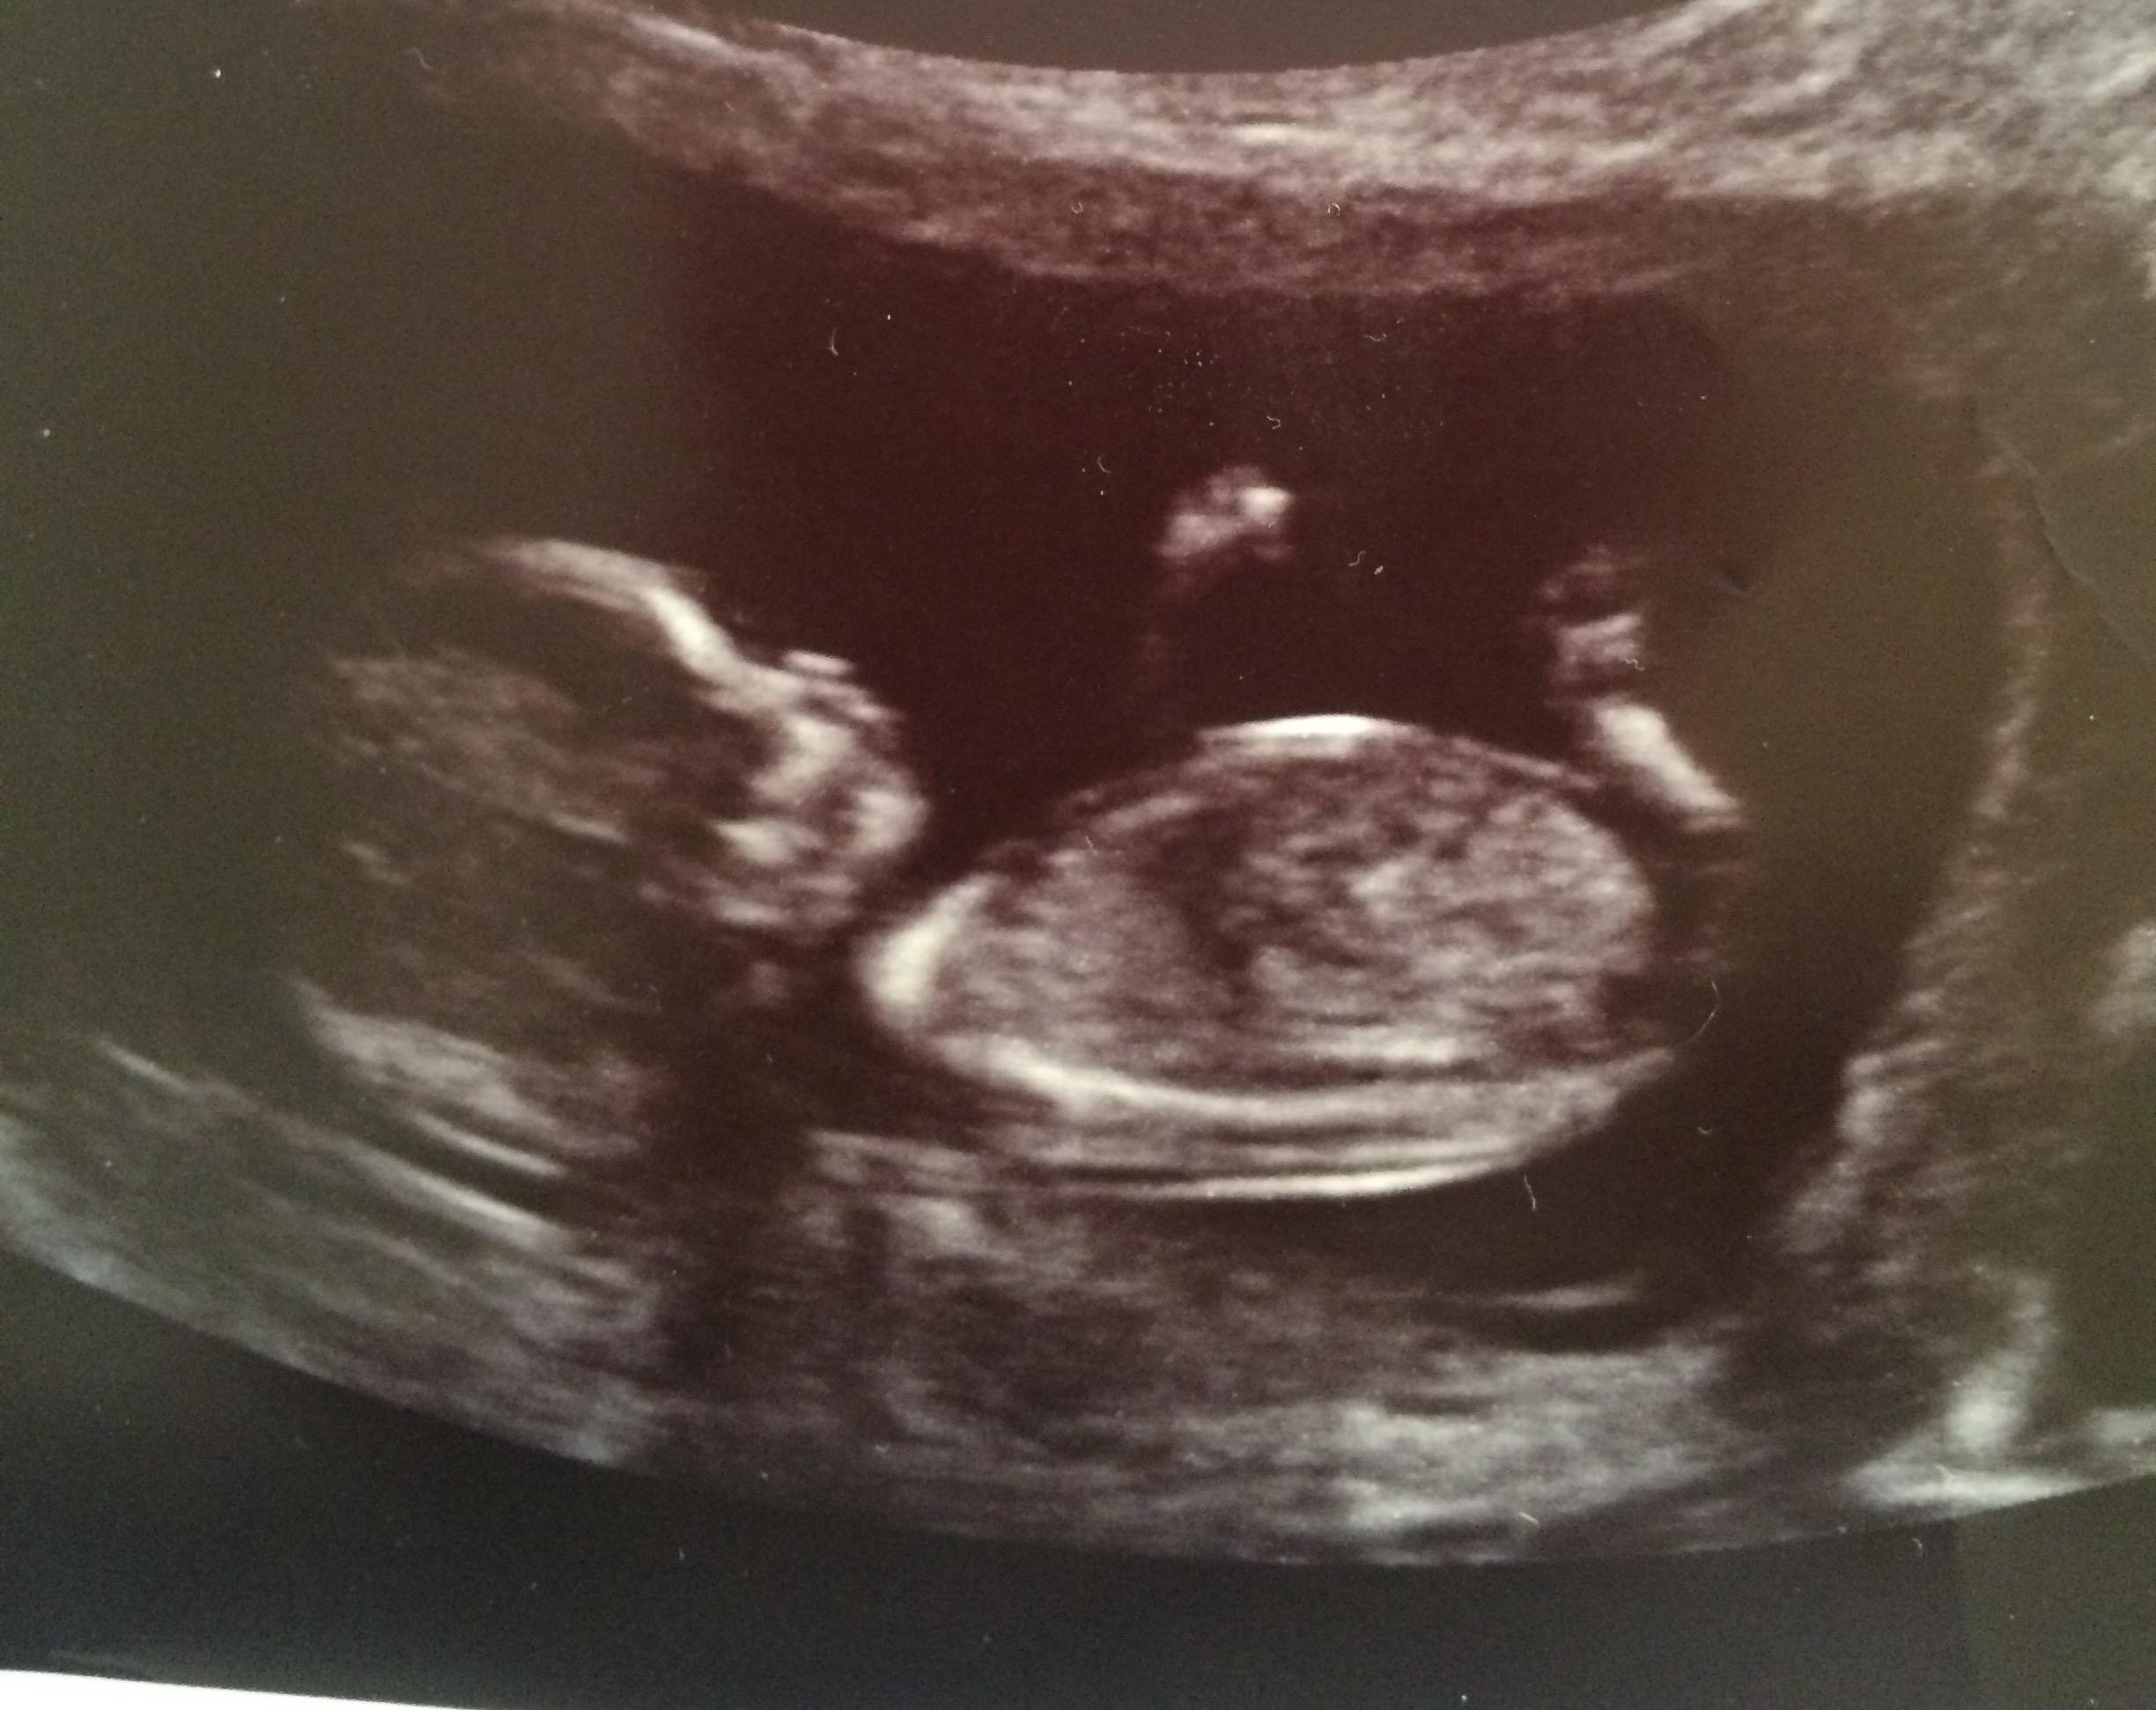

Any ideas on mine please at 12 weeks? Thanks xx

Attachment 36036

Attachment 36037